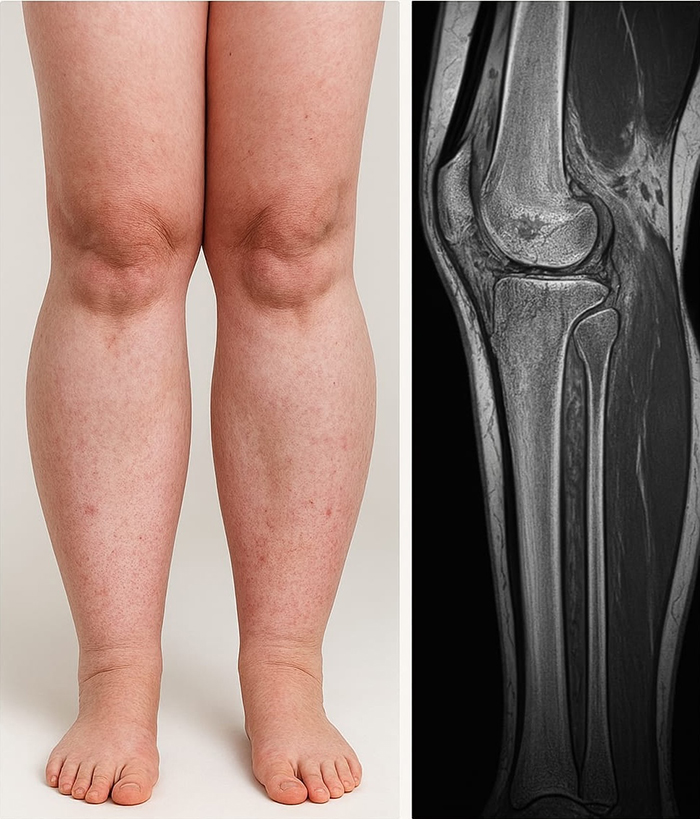

Muchas personas confunden el linfedema con el lipedema, no siendo lo mismo si bien tienen algunos puntos en común. El linfedema nos habla de una acumulación de líquido por obstrucción de la linfa, mientras que el lipedema se refiere exclusivamente a grasa y suele causar dolor, hematomas y sensibilidad en la zona.

El lipedema no se da en pies ni manos, sin embargo, el linfedema, sí. El doctor Hamidreza Eskandari, CEO y director de la clínica madrileña Golden Estética, nos cuenta cómo tratar de la mejor manera ambas problemáticas desde su punto de vista médico-estético.

A diferencia del lipedema, que es simétrico, doloroso a la palpación y afecta casi siempre a ambas piernas, el linfedema presenta un signo clínico característico: el signo de Stemmer positivo, que indica dificultad para levantar la piel en la base de los dedos. La hinchazón o celulitis por grasa localizada suele ser blanda, reversible con el reposo y no presenta la misma evolución ni las alteraciones del drenaje linfático. En casos dudosos, el diagnóstico se debe apoyar con pruebas como la linfogammagrafía, el linfoscintigrama o la linfografía con ICG.